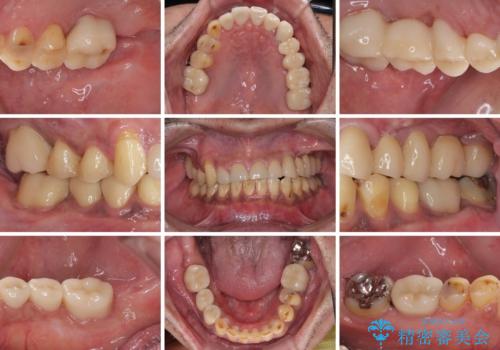

矯正治療は想定通り長期化しましたが、しっかりと奥歯の咬み合わせを向上させて前歯の被蓋を改善させることができました。

目立つ銀歯やすり減った前歯がセラミッククラウンとなり、患者様には大変満足していただけました。